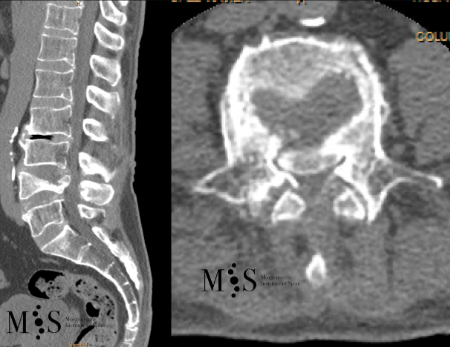

Example Clinical Case: Kyphoplasty

Pre- and post-operative comparison of a cemented kyphoplasty

Female, age 55, compression fracture of L2

After 1

after 2